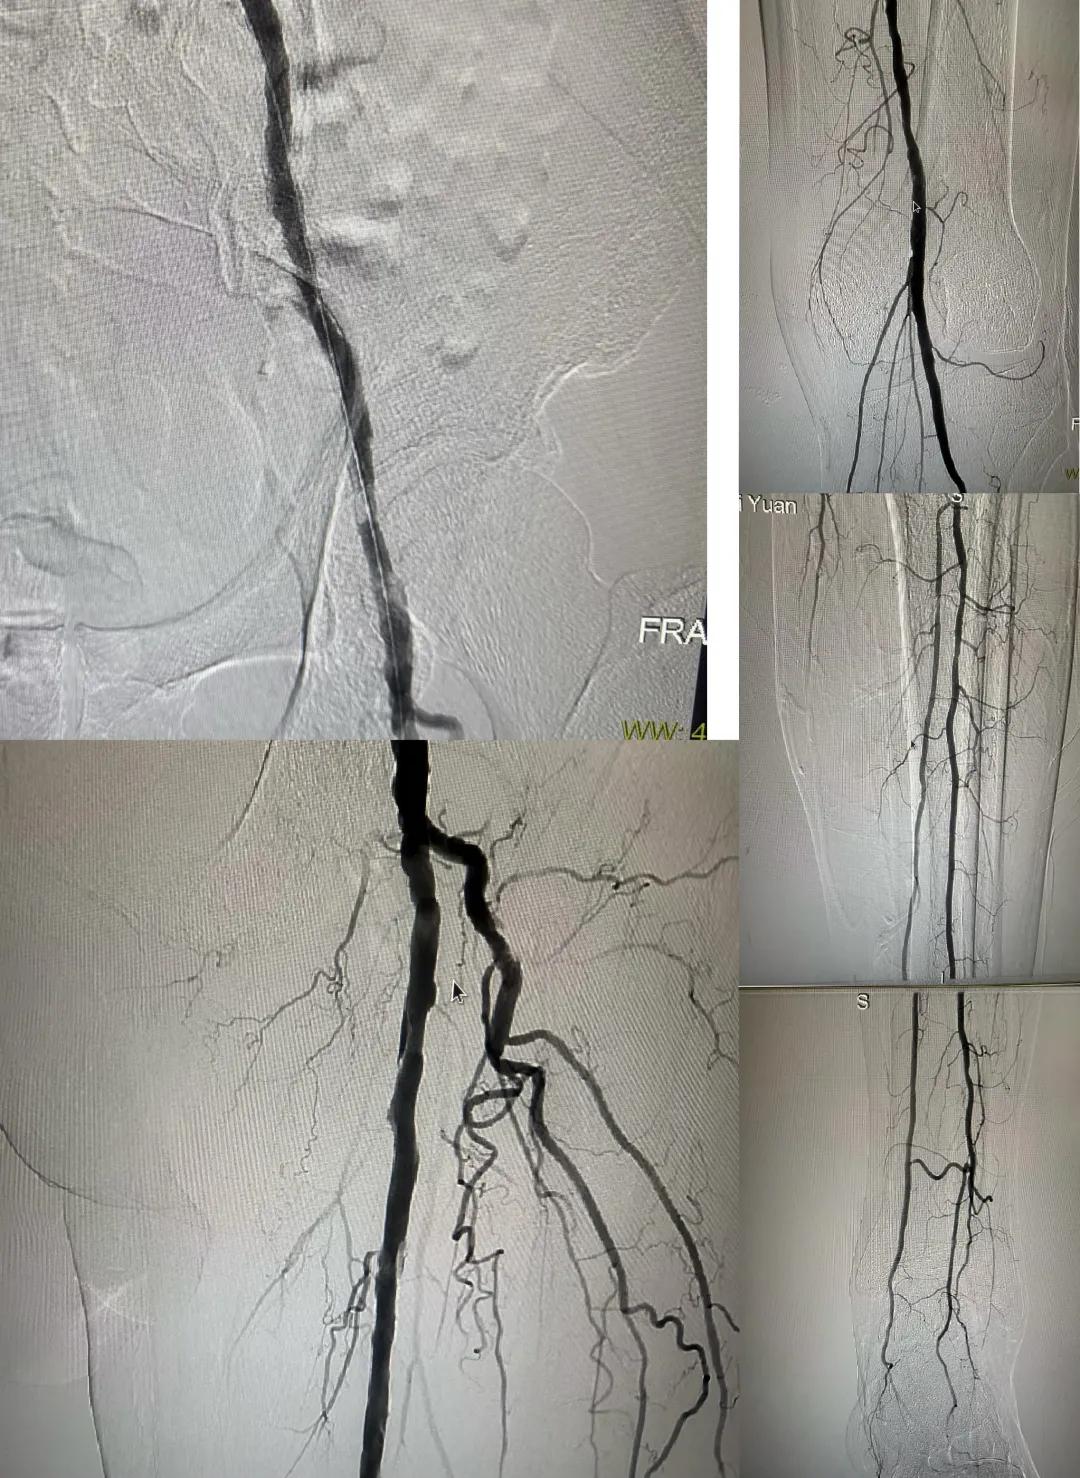

患者,男,73歲,約15天前出現(xiàn)左側(cè)腳面腫痛,間歇性跛行,左足第三足趾壞疽,遂來市中醫(yī)院就診,以“下肢動脈硬化閉塞、糖尿病足壞疽、”收住外二科,評估患者病情后需實施左下肢球囊擴張成形術。術中造影見患者左側(cè)髂動脈、股淺動脈階段性重度狹窄。經(jīng)外周球囊擴張術后,再次造影見股淺動脈、髂動脈血流通暢,膝下及足部血流速度較前改善。

術后已疏通血管成像